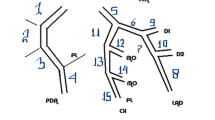

According to the criteria of North American symptomatic carotid endarterectomy trail (NASCET)[10], carotid and cerebrovascular arteries were divided into 40 segments including common carotid artery (CCA), carotid bifurcation (CB), external carotid arteries, internal carotid arteries (ICA) (C1-C7), extracranial vertebral artery (eVA), intracranial vertebral artery (iVA), basilar artery (BA), anterior cerebral artery (A1, A2), middle cerebral artery (M1, M2), posterior cerebral artery (P1, P2), anterior communicating artery (ACoA), and posterior communicating artery (PCoA). These segments were also divided into 3 categories, including extracranial arteries (CCA, CB, CA, C1, and eVA), intracranial ICA (C2-C7), and intracranial arteries(iVA, BA, A1, A2, M1, M2, P1, P2, ACoA, and PCoA). Only segments with a diameter >1.5 mm (as measured on the MDCT angiogram) were included. The type of plaque was determined using the following classification proposed by Ballotta E et al.[11]: 1) non-calcified plaques, plaques having lower density less than 50 HU; 2) calcified plaques, Plaques with a mean attenuation of 130 HU or greater; and 3) mixed plaques, plaques with a mean attenuation of 50-129 HU (Figure 1). A grade of stenosis was assigned for each chosen segment: grade 0 for normal or no observable plaque, grade 1 for diameter stenosis <30%, grade 2 for 30%–69% diameter stenosis, grade 3 for plaques with 70%–99% diameter stenosis, and grade 4 for 100% occlusion (Figure 1)[10]. Finally, it was determined whether the plaque was obstructive or not, using a threshold of 70% luminal narrowing. Each vessel was analyzed on at least two imaging planes, one parallel and one perpendicular to the course of the vessel, and the vessel diameters were measured on perpendicular to the vessel course. For each patient the number of diseased segments, type of plaque and degree of stenosis were determined and recorded.